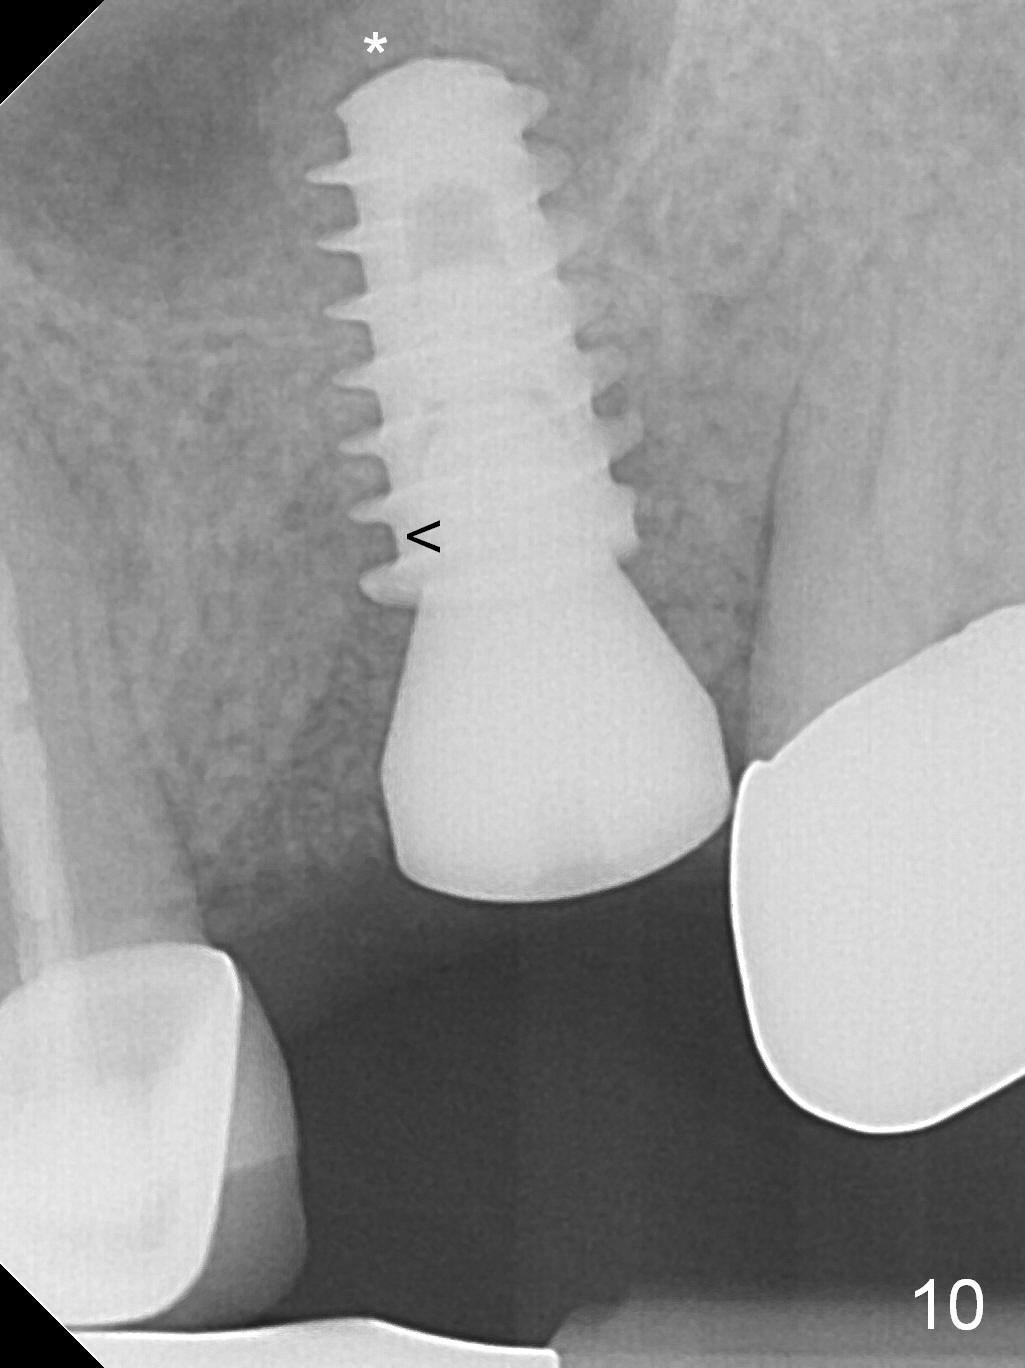

The patient is doing well 9 days postop.  The immediate provisional is loose and over-sized.  It is removed for trimming and reline; the socket and bone graft (Fig.8 *) are healing.  It appears that an angled abutment is required next time of provisional revision.  When an angled abutment is being placed 23 days postop (Fig.9), it appears to wiggle the implant due to its long leverage.  Instead a healing abutment is placed.  The implant is unstable 4.5 months postop with seemingly excessive bone-implant gap (Fig.10 <).  The 5.5x9 mm implant is removed.  A 5x17 mm tap is used to change the trajectory and sinus lift, followed by 6x17 one (Fig.11).  Finally a 6x14 mm tissue-level implant is placed with insertion torque > 50 Ncm (Fig.12; vs. <20 Ncm (Fig.7,10)) and improved trajectory.  An immediate provisional is fabricated to prevent the mesial drifting of the tooth #15 (Fig.13 P (*: occlusal clearance)).  By using the taps and placing the longer implant, the sinus lift is more obvious (compare Fig.10 and 12 (*)).  Sinus lift remains evident 3.5 months postop (Fig.14) with apparently osteointegration (Fig.15).